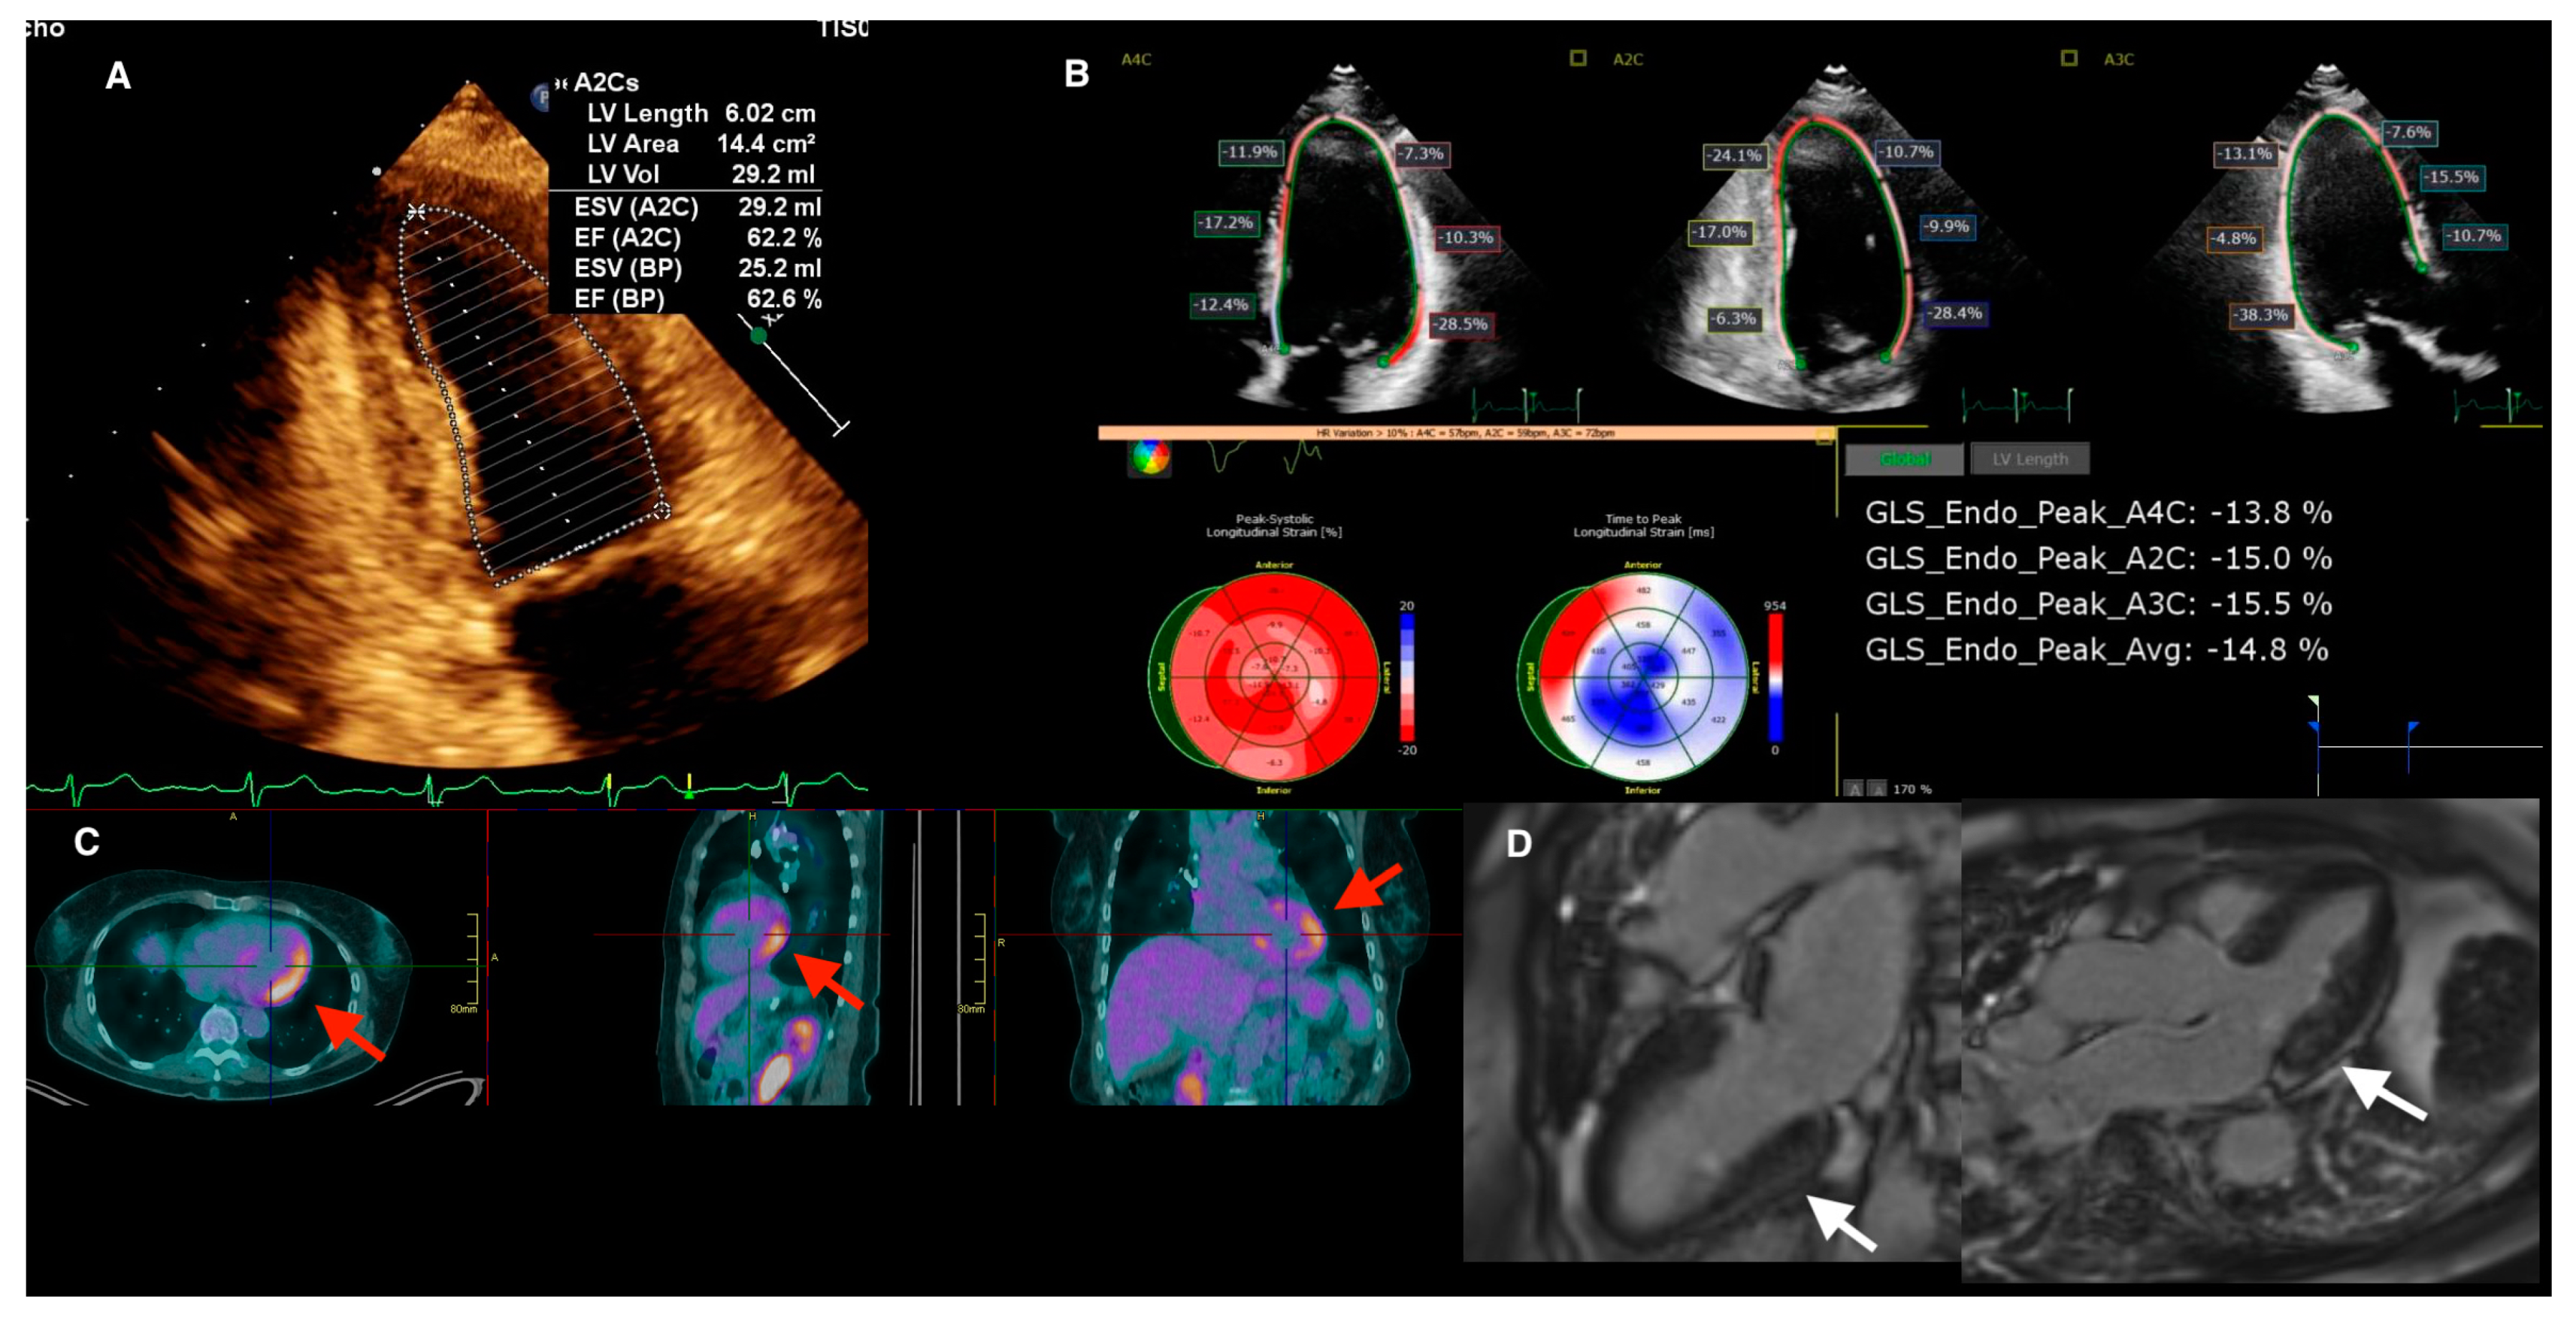

- Okafor, J.; Azzu, A.; Ahmed, R.; Cassimon, B.; Wechalekar, K.; Wells, A.; Kouranos, V.; Baksi, A.J.; Sharma, R.; Guha, K.; et al. A rare case of extensive biventricular cardiac sarcoidosis with reversible torrential tricuspid regurgitation. J. Nucl. Cardiol. 2023. [Google Scholar] [CrossRef]